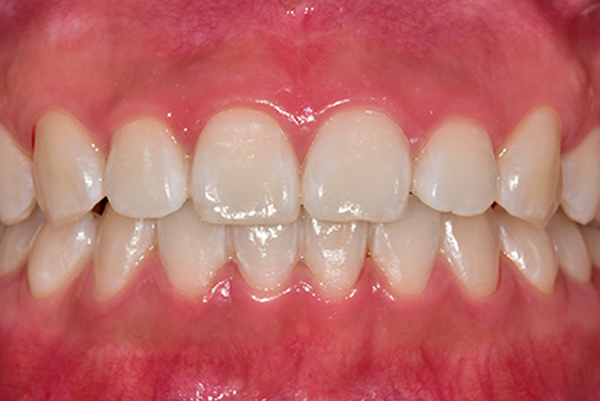

디아트 테라피, 실제로 받아보니 어땠나요?

예방관리 받고 나서 잇몸도 좋아지고,

웃을 때 더 예뻐진 것 같아요. 처음엔 "굳이 해야 돼?" 싶었지만,

비싸게 심은 임플란트 관리 못 하면 더 손해라는 걸 알았죠.

“진짜 하늘을 나는 기분이었어요. 고맙단 말밖에 안 나와요.”

- 이○○ 님 인터뷰 中